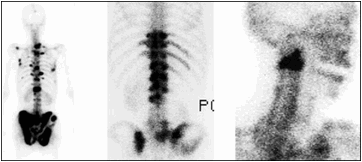

骨転移を診断するために、特定の検査が行われる場合があります。これらには、骨髄機能とカルシウムレベルを検査する血液検査や、X線、骨スキャン、CTスキャン、MRIスキャンなどの画像検査が含まれます。